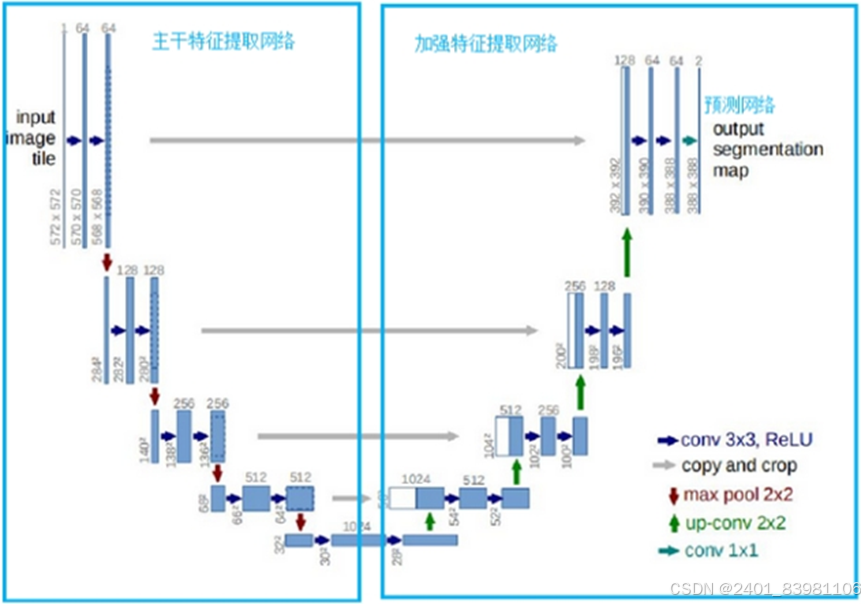

图像分割:基于深度学习的舌头图像分割模型主要分为两类, 82 一个是U-Net83,84和 Seg-Net85,86从全卷积网络(FCN)演化而来,另一个是从CNN改进而来的Mask R-CNN, 87 广泛应用于各种类型的医学图像分割

- 深度学习方法:使用深度学习模型进行语义分割,如U-Net、Mask R-CNN,GraphCut,FCN2s 但如U-Net内存过大,不易部署到移动端,如下几种分割效果:

2:语义分割算法是用一个与相邻像素类别和该像素点所属的整体类别相关的类别来标记图像的每个像素点,如U-net,seg-net

U-NET语义分割模式图

(U型状)

U-Net与判别滤波学习多任务联合的CNN模型,用于不同类型的舌苔分类识别, 分类F1-